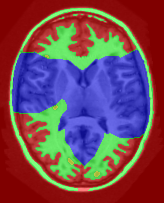

![]() |

| (a) tree and min-margins | ||||

|

Subject 3 |

Subject 4 |

| ground truth | a-exp [7, 8] | QPBO [25, 8] | ours | |

Brain Segmentation:

We combined the labeled regions in dataset [19] (T1W MRI) to create the tree shown in Fig. 15(a). In this setting, the data term is the sum of color model penalty and an shape prior [5] based on an automatically extracted brain mask using [16],

where is the intensity at pixel and is the Euclidean Distance Transform of the extracted brain mask. Min-margins are shown in Fig. 15(a). We also added a Hedgehog prior [13] for the sub-cortical grey-matter to help our energy differentiate between grey-matter and sub-cortical grey-matter.

In this application our method outperformed QPBO in most cases and a-exp in all cases. In fact a-exp always converged to a weak local minima in this setting, see Fig. 15. Based on our experience the quality of a-exp result depends on various factors, e.g. tree complexity, the number of min-margins introduced, the order in which labels are expanded, and the initial solution. For the subjects that QPBO was able to find the global optimal Path-Moves either found the global optimal or a very close solution.